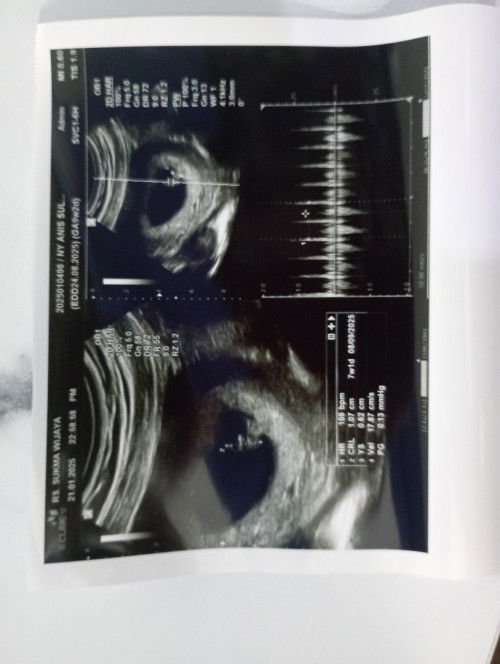

Usia kehamilan berbeda antara di bidan dan dokter

Maaf mau sharing dan bertanya kepda bunda2 yg lg hamil. Brusan sy dri dokter telah melakukan USG ternyata usianya masih 7minggu sedangkan di bidan 9minggu. Apakah itu normal?

Klo usg usia 8week udh keliatan gk janinnya?

Soalnya sy mau usg takut yg keliatan cuma kantong aja